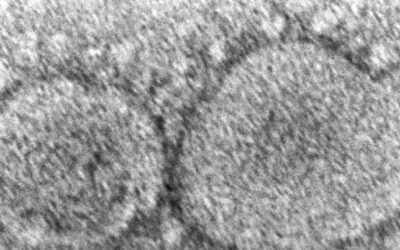

EEUU: Cámara vota hacer públicos orígenes del COVID-19

La Cámara de Representantes estadounidense votó por unanimidad el viernes para hacer pública la...